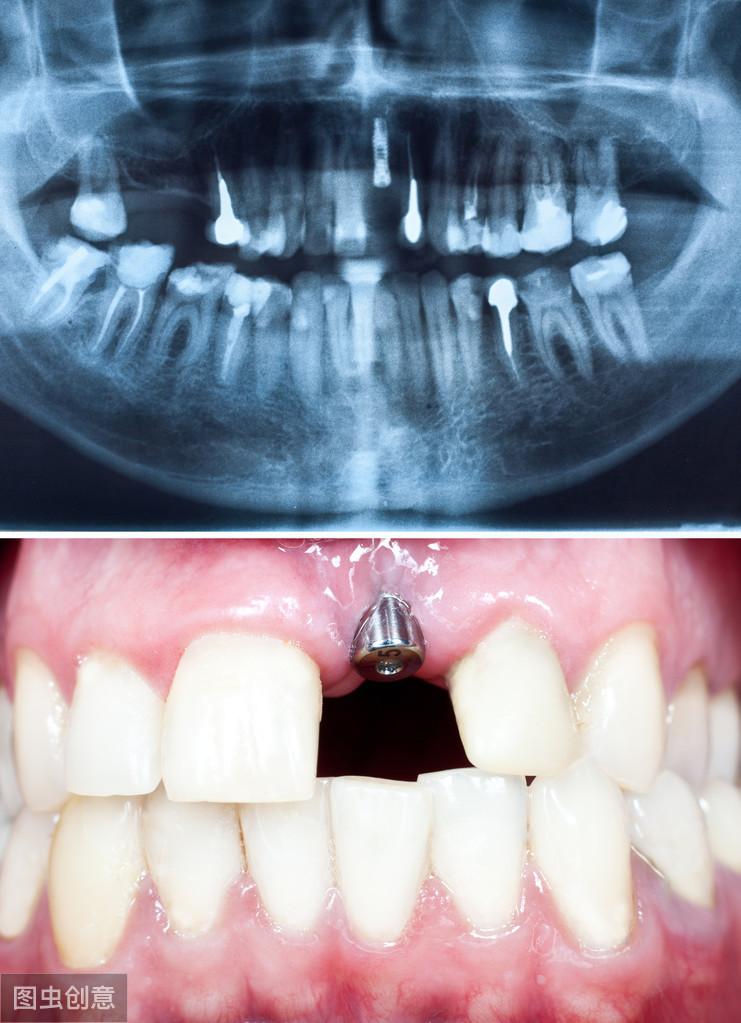

1. 口腔檢查:術(shù)前的口腔檢查很重要,如果有齲齒或其他牙周疾病,不提前進(jìn)行調(diào)節(jié)就可能會(huì)引起種植體感染,造成種植手術(shù)失敗,所以一旦口腔檢查時(shí)發(fā)現(xiàn)有口腔問題,應(yīng)先進(jìn)行調(diào)節(jié),尤其是齲齒等病灶牙;

如果沒有需要調(diào)節(jié)的口腔問題,就可以進(jìn)行牙槽骨估值檢測(cè),因?yàn)榉N植體是直接植入牙槽骨的,所以骨質(zhì)的好壞也是決定能否接受牙齒種植的關(guān)鍵性因素。